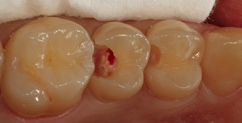

Bei der 55-jährigen Patientin imponierte eine okklusal penetrierte Sekundärkaries an dem Goldinlay an Zahn 15 (Abb. 8). Nach Aussage der Patientin war der Zahn seit ein paar Wochen aufbissempfindlich; die Vitalität war gegenüber Zahn 14 und 16 reduziert. Hieraus ergab sich die Behandlungsindikation zur Entfernung des Inlays und zur Vorbereitung einer endodontologischen Therapie. Nach der Entfernung des Inlays imponierte ein massiver Kariesbefall im gesamten Kavitätenbodenbereich (Abb. 9). Nach der Exkavation zeigten sich eine Verbindung zur Pulpa als auch diverse Infraktionslinien (Abb. 10). Die Verbindung zur Pulpa wurde interimsmäßig überkappt (TheraCal LC, Abb. 11); die Trepanation des Zahnes wurde dem Endodontologen überlassen. Vor einer endodontologischen Behandlung ist eine dichte adhäsive präendodontologische Aufbaufüllung essenziell. SDR flow+ hat die Indikation zur Aufbaufüllung in seinem Indikationsspektrum.

Der Aufbau eines solchen Zahnes mit einem Bulk-Flow-Komposit in zwei horizontalen Inkrementen (Kavitätentiefe deutlich > 4 mm) erleichtert und verkürzt selbst bei zwei Polymerisationszyklen die Gesamtversorgungsdauer im Vergleich zu einem dualhärtenden Aufbaukomposit. Hinzu kommt, dass alle dualhärtenden Aufbaukomposite keine definitiven Füllungsmaterialien sind und später entweder wieder entfernt oder komplett von einer indirekten Restauration eingefasst sein müssen. Das Bulk-Flow-Komposit hingegen ist ein definitives Füllungsmaterial, welches später – nach der endodontologischen Versorgung – als Kavitätenbodenelevation [16,23,31,34,47,60] verbleiben kann. Somit schont man mit Sicherheit Zahnhartsubstanz, wenn eine komplette Entfernung von Komposit gerade in den Tiefen des approximalen Kastens vermieden werden kann. Die Abbildung 12 zeigt den in zwei Inkrementen SDR flow+ in der Farbe A3 aufgebauten Zahn 15. Der Zahn ist so für den Endodontologen optimal vorbereitet. Die Abbildung 13 zeigt einen Ausschnitt aus der endodontologischen Diagnostik-Aufnahme und verdeutlicht die sehr gute Röntgenopazität sowie das sehr gute approximale Adaptationsverhalten.